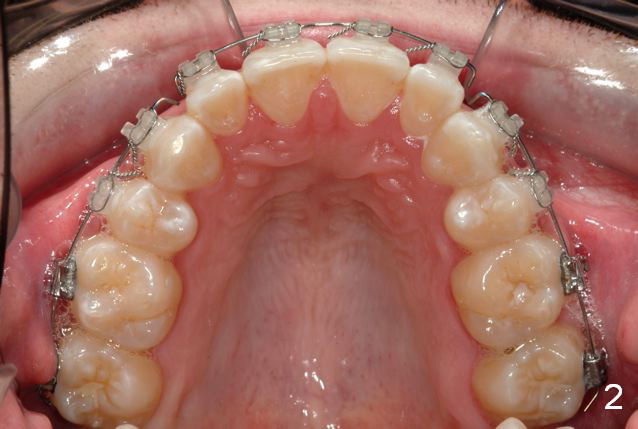

Initial bonding on 08/04/2014 (Fig.1-3); follow up appointments (09/20/2014 (Fig.4,5); 11/11/2014 (Fig.6,7), prepared for maxillary segmental surgery to expand, advance, and level.

I routinely start off with a round NiTi AW, like .014 in the .018 slot, then to .016 and up to 16X22 NiTi. Then I go to rectangular SS.  I segmented the AW to facilitate the surgery.

What is advantage to segment AW initially (in the 1st appointment of bonding, Fig.1,2)?

Avoids compensating teeth and building in instability in a surgery case.

A continuous AW would align AND 'level'. The rule is never move teeth before surgery in a direction they will be corrected at the time of surgery. This concept we may need to talk in person.